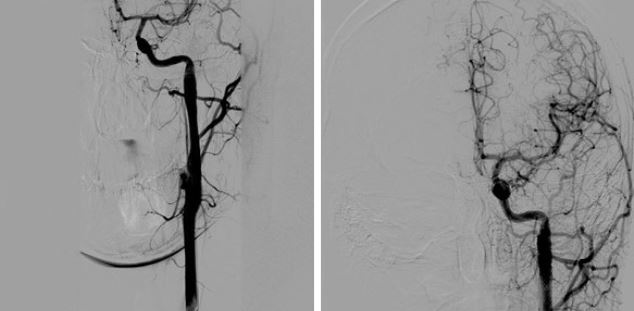

Верифицированный пристеночный тромбоз каменистого сегмента левой ВСА (неровность внутренних контуров, дефекты заполнения; рис. 2) потребовал установки дистальной защиты SpiderFX и стентирования левой ВСА в каменистом сегменте стентом CRISTALLO 7×10×30 мм с последующей постдилатацией (рис. 3).

Рис. 2. Диссекция (неровность внутренних контуров, дефекты заполнения). Установлен стент WALLSTENT проксимальнее области диссекции

Рис. 3. Имплантация стента CRISTALLO с последующей постдилатацией

Рис. 4. Контрольная цереброангиография